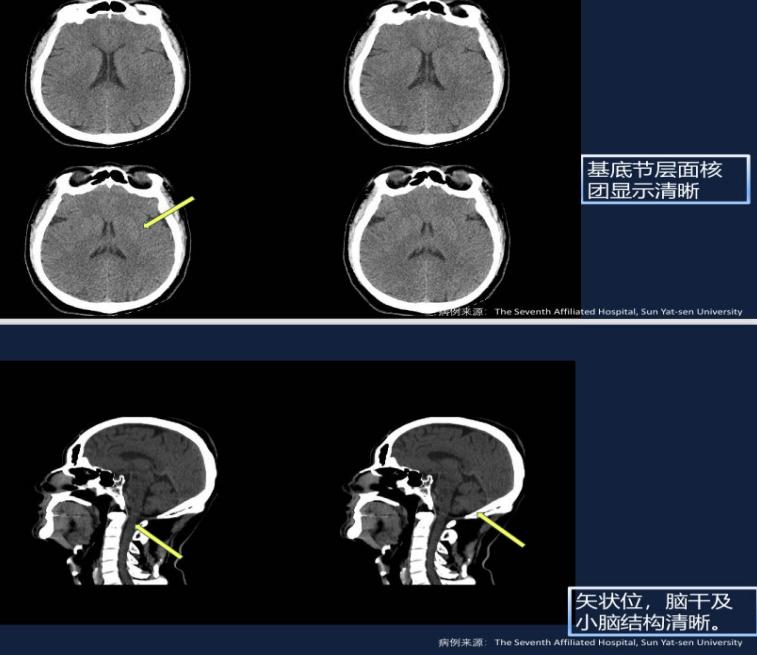

优点一:图像清晰

与老款SPECT相比,该款光子发射断层及X射线计算机体层摄影成像系统 (SPECT/CT)的图像更加清晰: